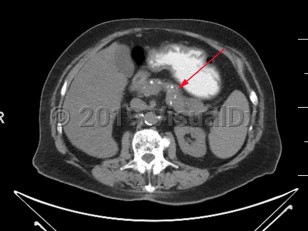

The diagnosis of chronic pancreatitis can be challenging and relies on a combination of symptomatology, histologic, radiographic, and endoscopic findings. There is no single gold standard test to confirm the diagnosis. Some patients present with recurrent episodes of epigastric abdominal pain and pancreatic enzyme elevation, while others can present with asymptomatic diabetes mellitus and be found to have chronic pancreatitis. Regardless of the predisposing medical condition precipitating the development of chronic pancreatitis, radiographically, pancreatic atrophy and calcification with a dilated pancreatic duct are often but not always seen. Histologically, pancreatic fibrosis, duct distortion, and intra-ductal calcification are often but not always appreciated.